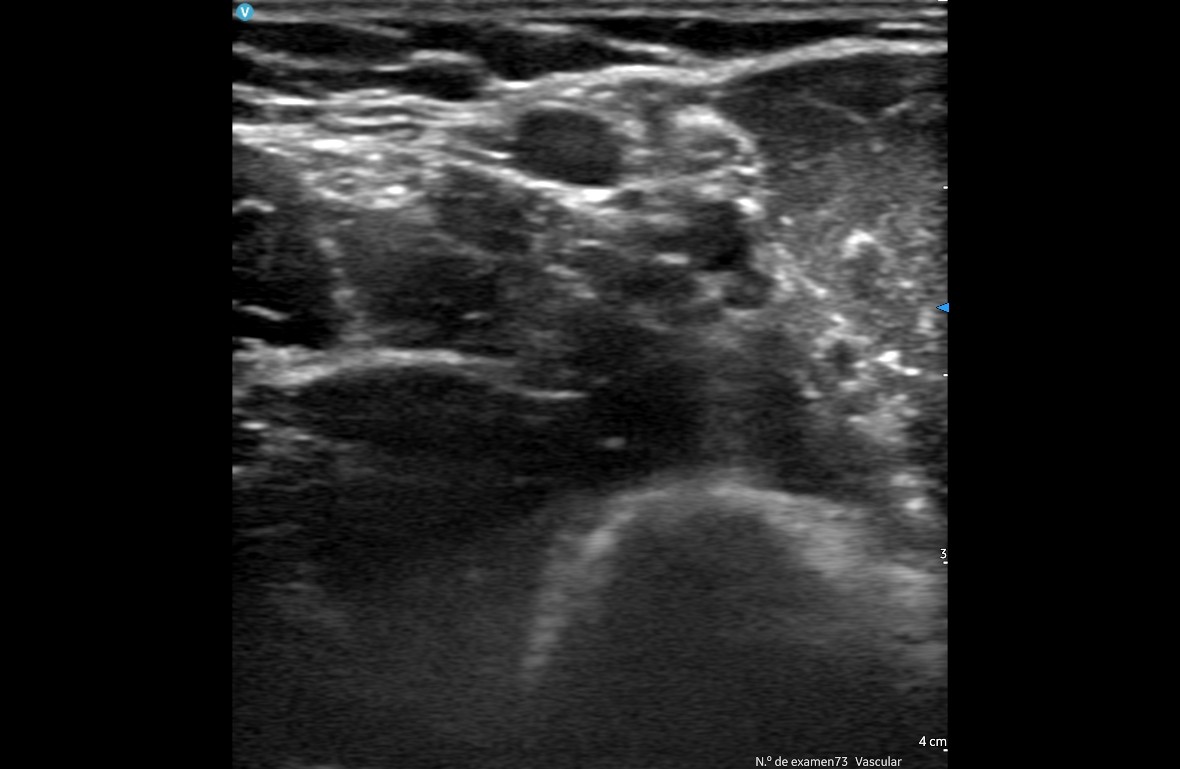

Otros usos, aunque en menor medida, han sido control de ascitis, valorar retención de orina, valorar hidronefrosis, descartar trombosis venosas profundas y en pocas ocasiones control de abscesos o infecciones de partes blandas.

A nivel de Enfermería se ha hecho uso principalmente para la inserción de catéteres venosos en el domicilio, sobre todo para el uso de antibióticos de larga duración y descartar trombosis venosas secundarias al catéter.